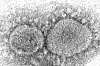

Dette elektronmikroskopbildet fra 2020 fa Center for Disease Control and Prevention (CDC) viser SARS-CoV-2-viruspartikler, som forårsaker COVID-19.